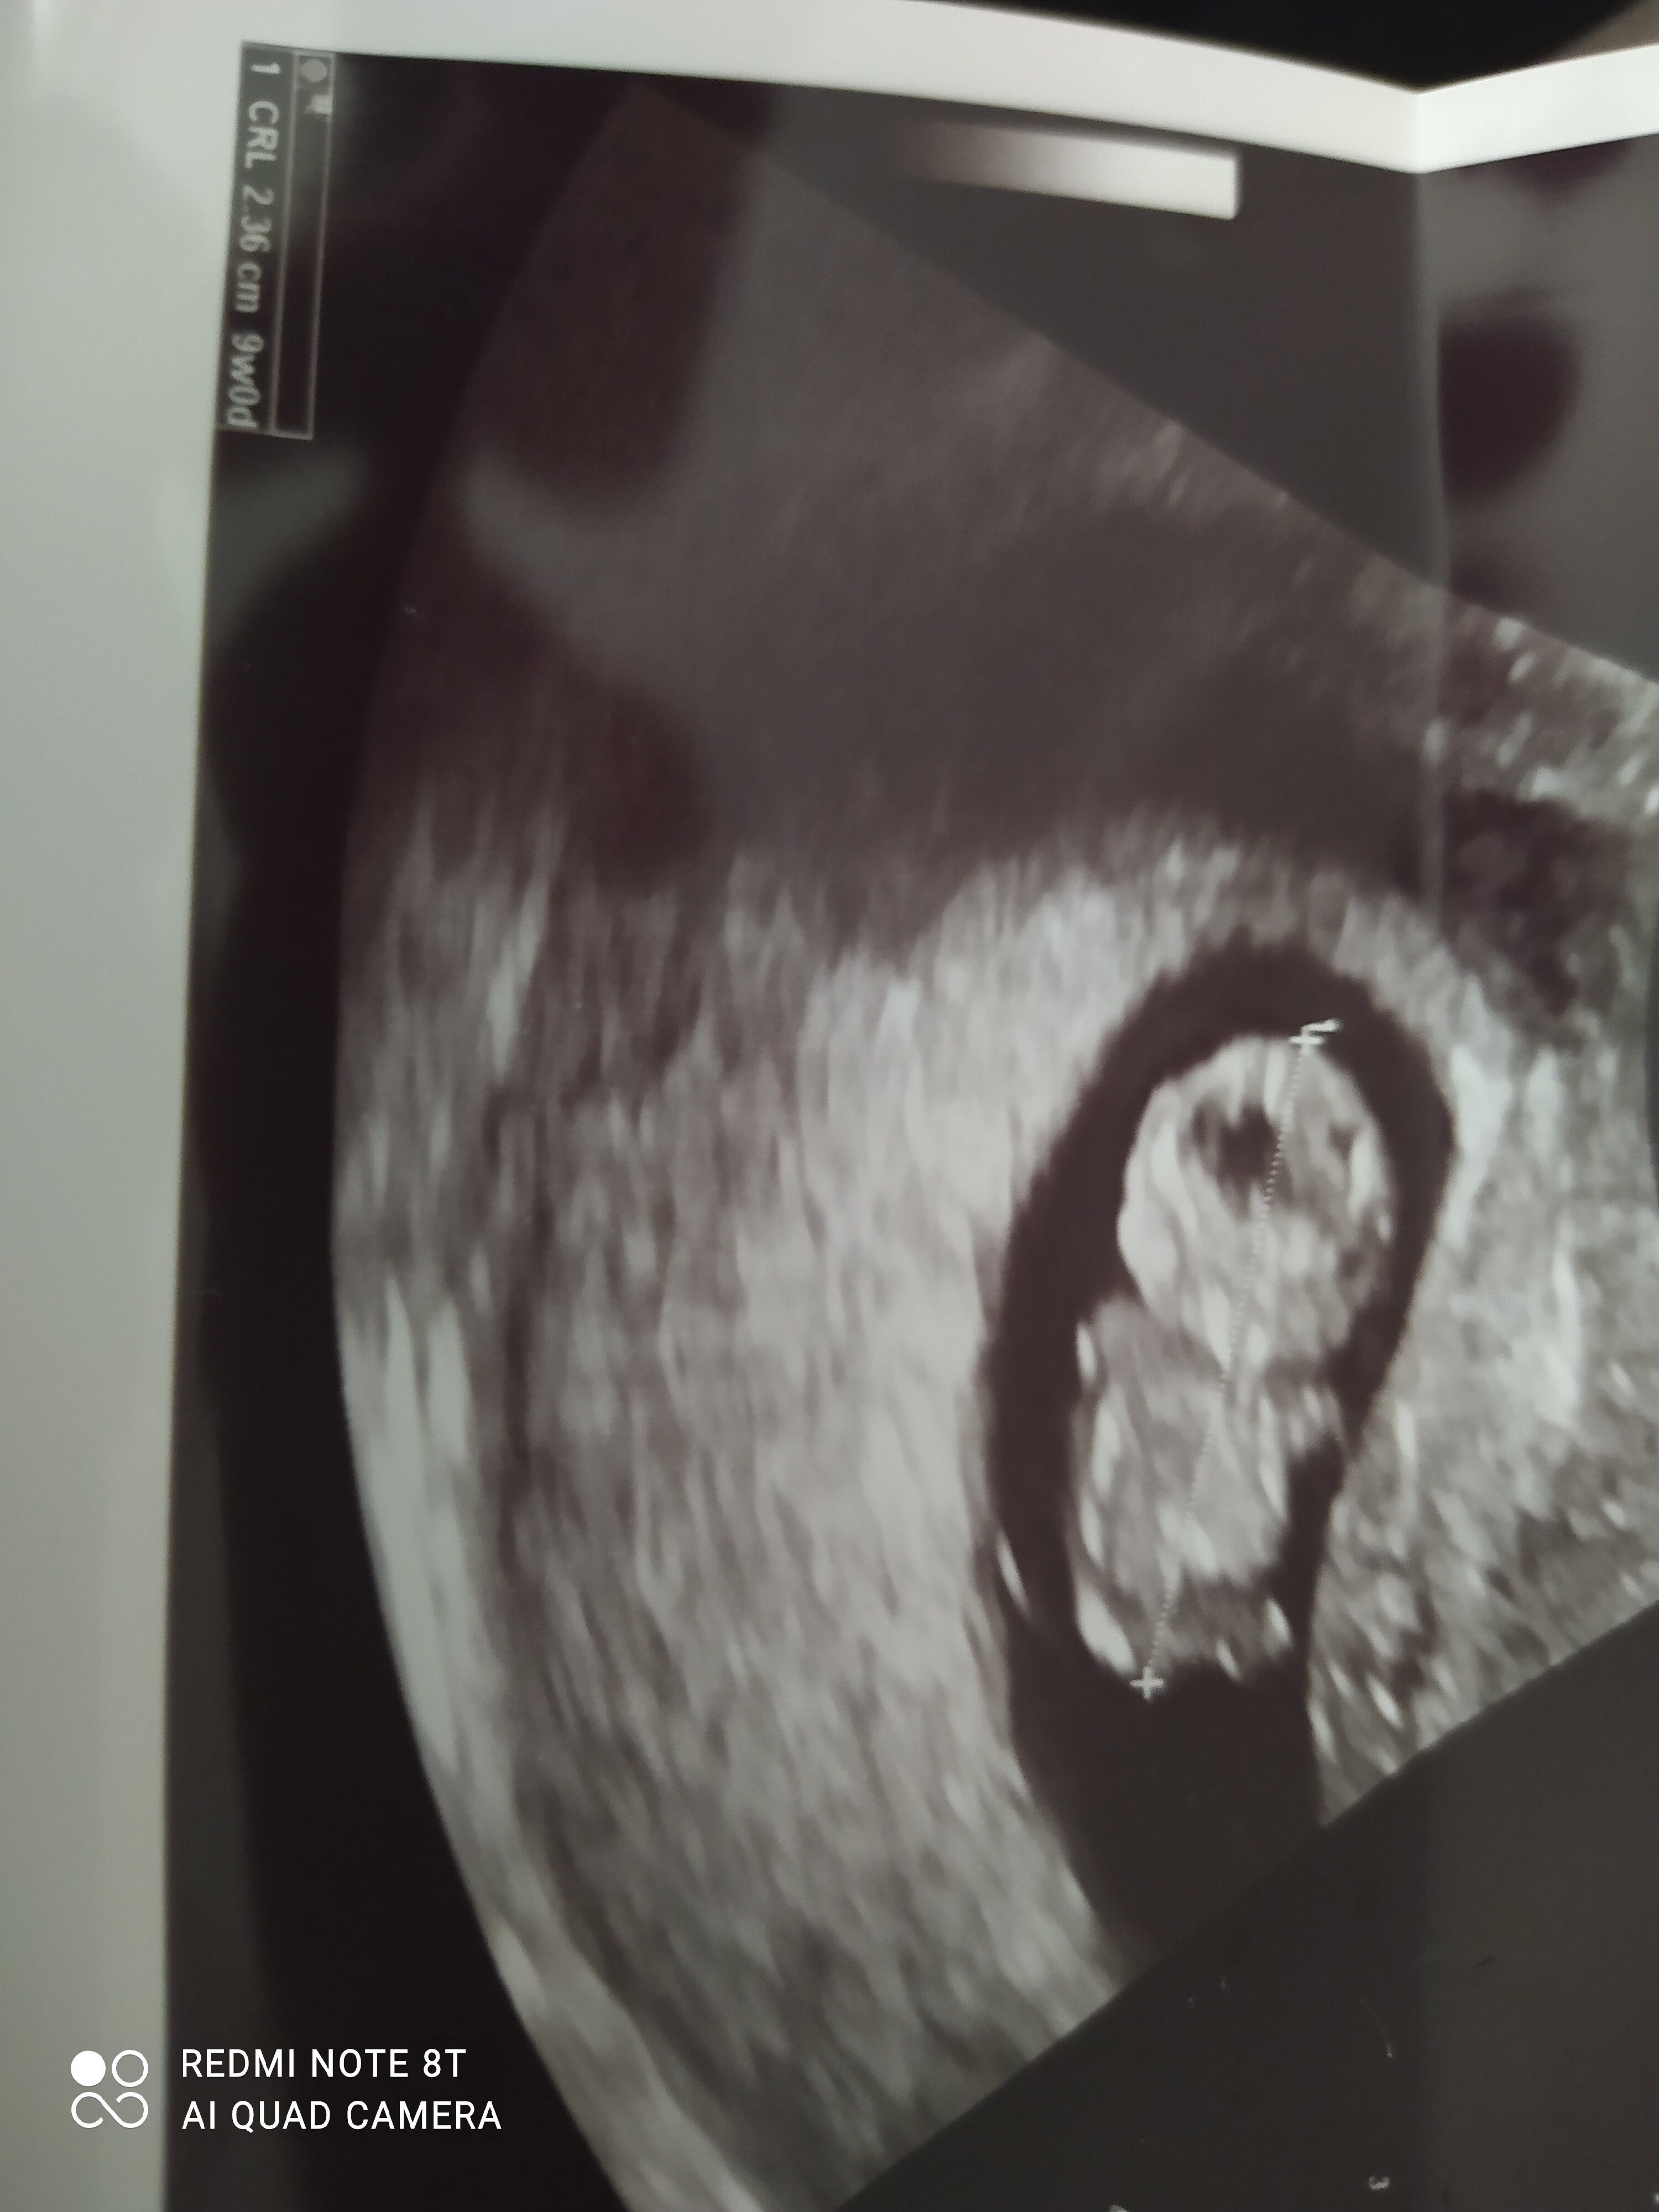

2,4 cm radości. Zdjęcie po dzisiejszej wizycie!!!

Załączniki

• 1646381137882723887015589035507.jpg